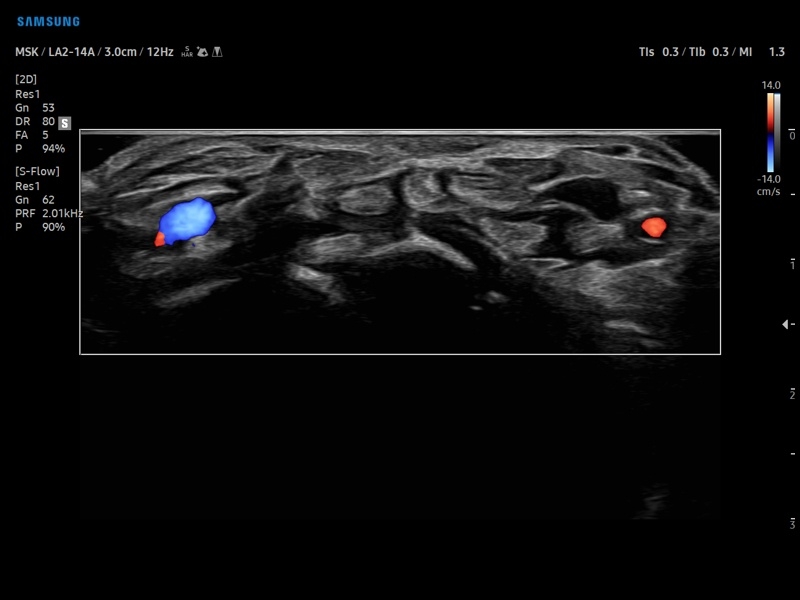

Недопплеровская визуализация кровотока:

• Модуль NerveTrack – автоматическое определение срединного нерва в поперечном сечении с использованием искуственного интеллекта.

• Модуль MV-Flow - программа (режим), позволяющая визуализировать кровоток в микроциркуляторном русле с высоким разрешением без использования контраста.